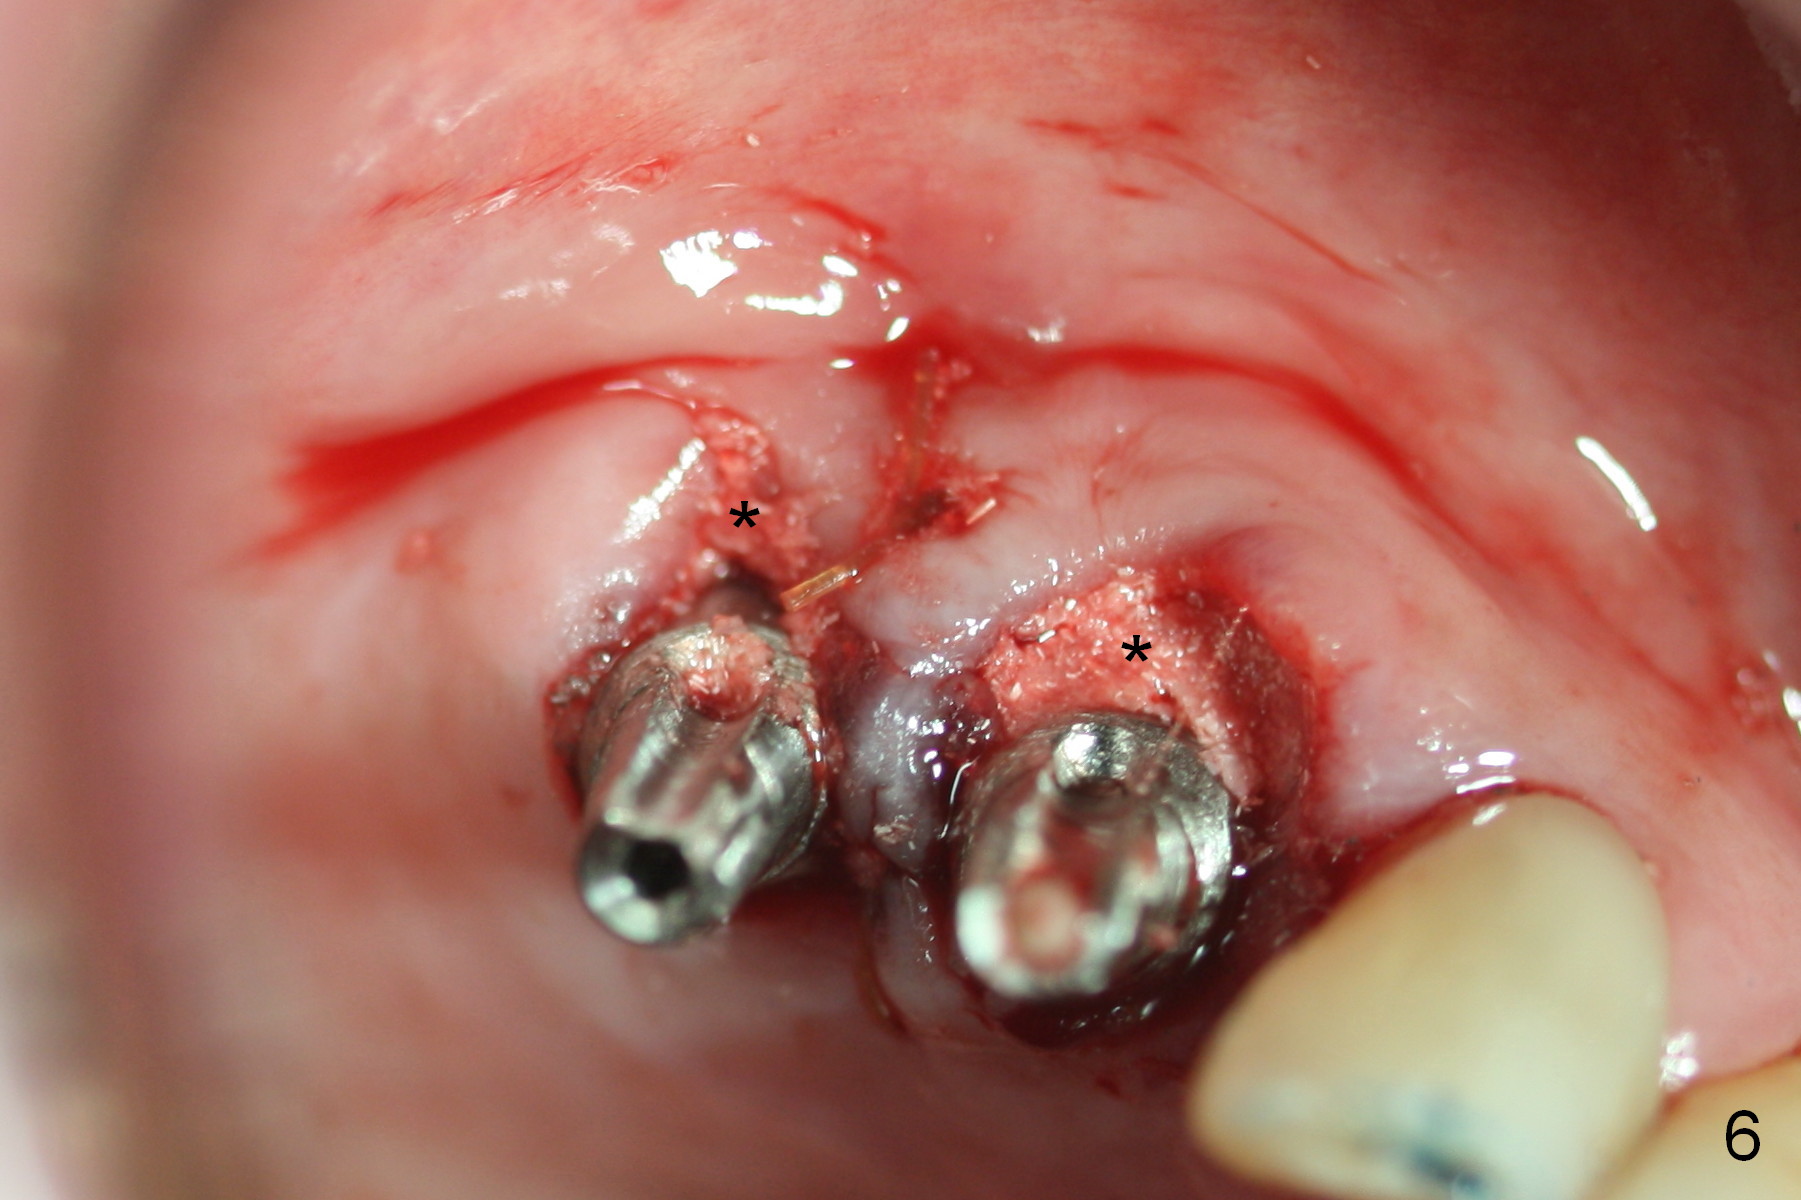

Several of CK's upper teeth (apparently in cross bite) are to be restored with implants (Fig.1). The first two are #5 and 6; note the oval roots (Fig.2). After extraction, and curettage, osteotomy starts in the palatal aspect of each socket. The 1st intraop PA shows that the trajectory at #6 is incorrect (Fig.3). After adjustment, osteotomies look parallel (Fig.4: D: 3.5x20 mm drill; T: 4.5x20 mm tap). This suggests how important it is to use parallel pins to check initial osteotomies for neighboring implants (Fig.3). The trajectory of the implants remains acceptable (Fig.5: 4.5x20 mm with insertion torque »60 Ncm); so is the position of the implants (as palatal as possible; Fig.6 (*: bone graft)). Immediate provisionals are fabricated in cross bite.